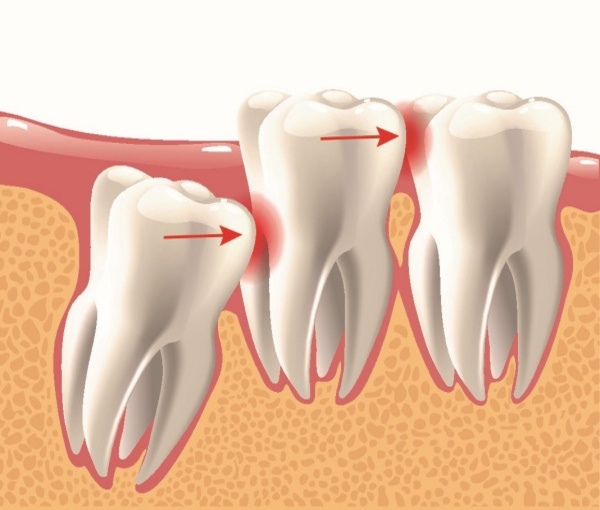

• Cung hàm không đủ chỗ: Đây là nguyên nhân phổ biến nhất. Khi răng số 8 bắt đầu mọc, toàn bộ các răng khác trên cung hàm đã ổn định vị trí. Nếu xương hàm của bạn có kích thước nhỏ hoặc các răng khác quá lớn, không còn đủ khoảng trống, răng khôn buộc phải tìm đường mọc theo hướng bất thường, dẫn đến mọc nghiêng, mọc lệch hoặc mọc kẹt, mọc ngầm hoàn toàn dưới nướu và xương hàm.

• Sự cản trở từ răng số 7: Răng 8 mọc ngầm thường gặp sự cản trở từ chân hoặc thân răng số 7 ở phía trước, khiến nó không thể trồi lên đúng vị trí thẳng đứng.